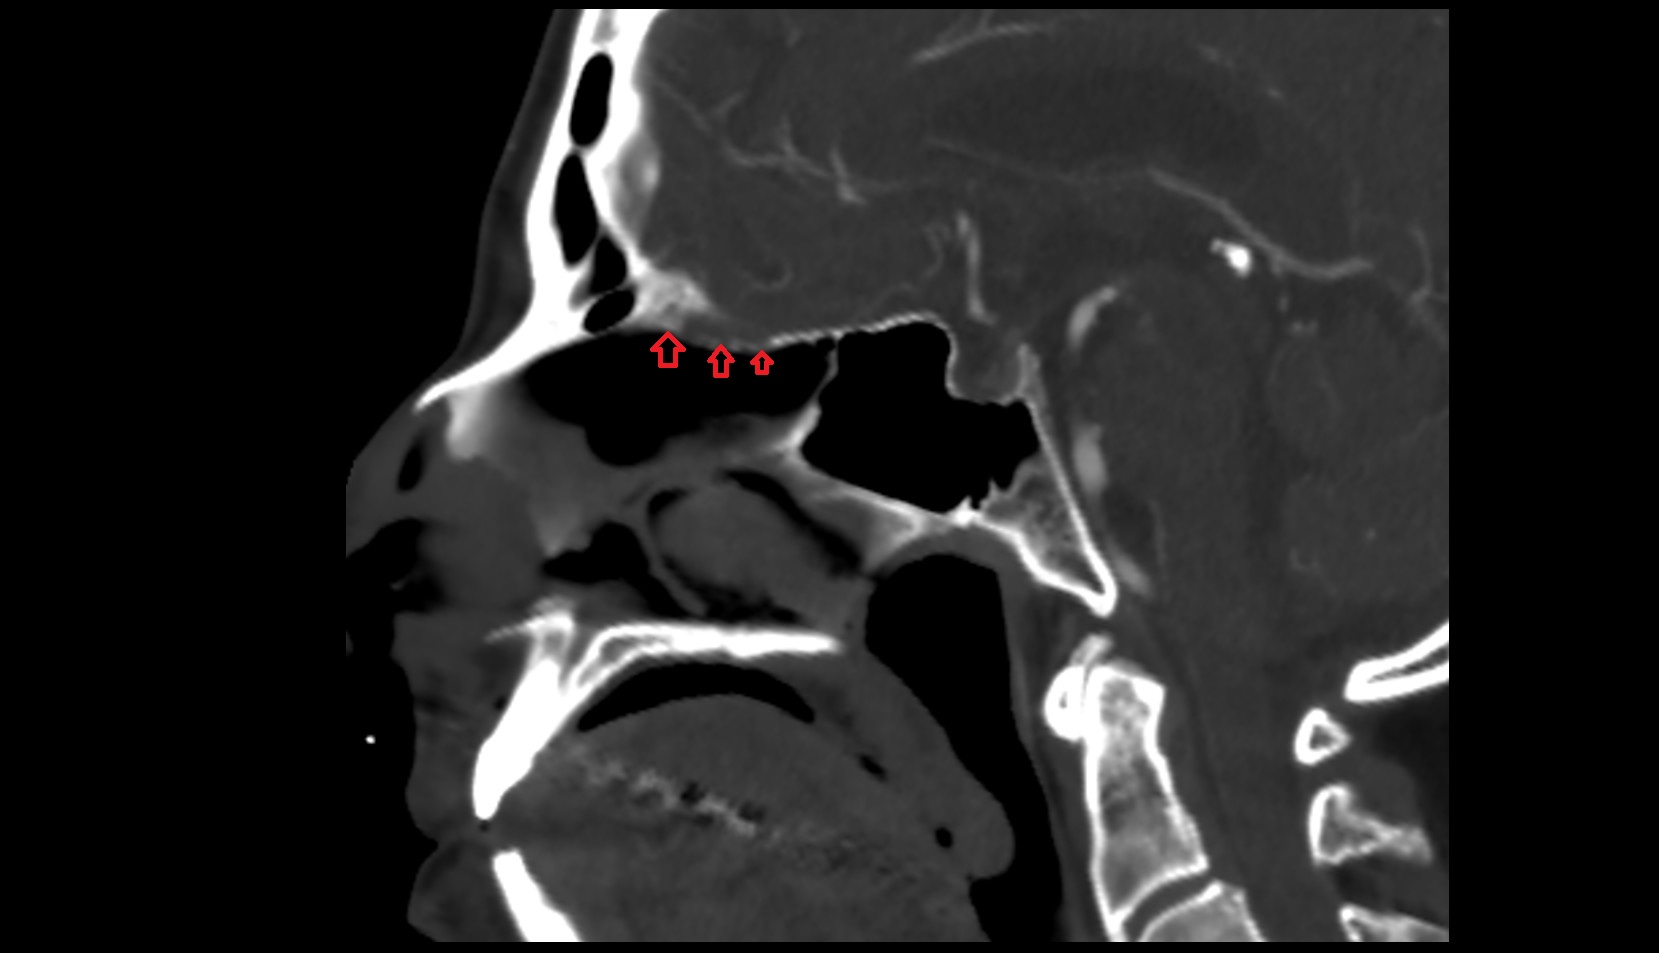

- Choana